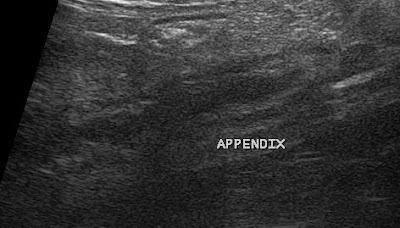

- Appendicitis